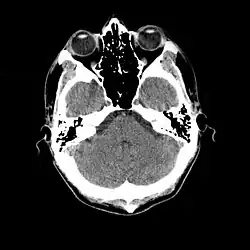

An slice through the head, showing the cerebellum, a small portion of each temporal lobe, the ears, the orbits, and the sinuses. Bone appears white on the black background; brain, eyeballs and ears are grey.

TC craneal normal.

La tomografía computarizada craneal (TC, inventada en 1972) demostró ser una excelente herramienta para diagnosticar neoplasias cerebrales en niños, incluidas las encontradas en la esclerosis tuberosa.[46]